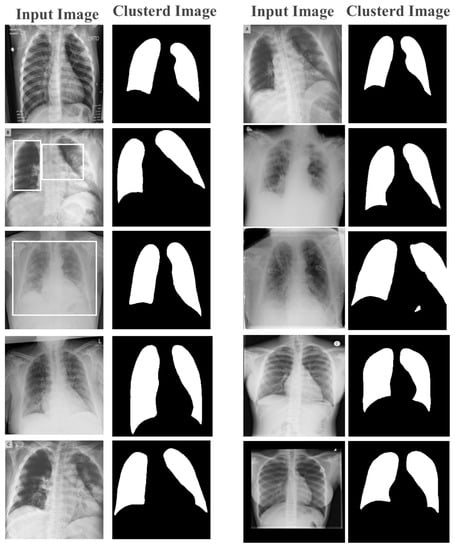

Stage 1: Image Clustering and Pre-Processing

- Number of Clusters: Selecting the optimal number of clusters in the advanced parallel k-means clustering was crucial for achieving effective cluster analysis. This is particularly true in the medical field, where the identification of meaningful clusters can lead to more accurate diagnoses and treatments. However, the traditional methods of finding k-value, such as the Elbow method or the Silhouette method, are not always sufficient in the medical field, where the data are often complex and high-dimensional. In such cases, expert knowledge could be required to identify clinically relevant subgroups, which could then be used to determine the optimal number of clusters. In this paper, the k-value set to 2 in the clustering of numeric and text data and set to 5 for image clustering, as there were 5 main gray-scale stages of colors in the X-ray and MRI images.